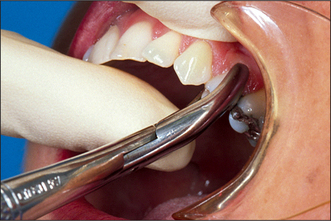

These forceps can be applied to the long axis of anterior teeth, gaining access by the patient opening their mouth fairly widely (Fig. 4.4). However, if one were to attempt to use these forceps on an upper first premolar, there is a risk of traumatizing the lower lip. Forceps for use in the upper jaw further back than the canine have a curve in the beak (Fig. 4.5), which keeps them above the lip when they are in the long axis of the tooth. The beaks of these forceps are also concave on their inner aspect to fit the root of upper premolars.

Fig. 4.4 Application of upper straight forceps to an incisor.